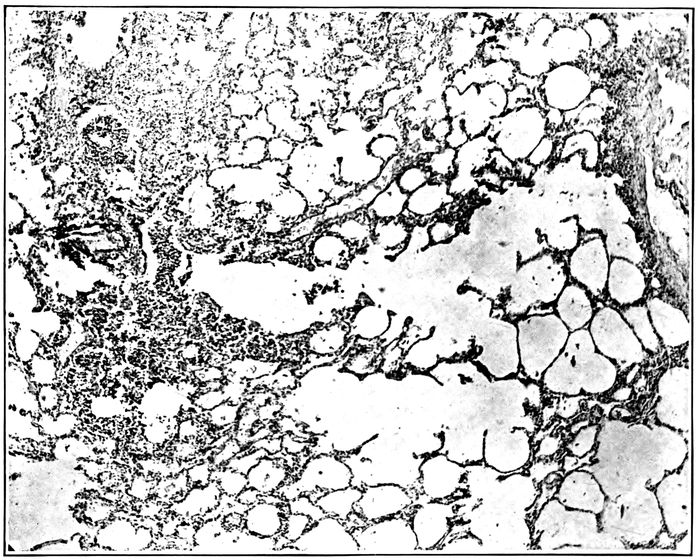

| 26. | Unresolved bronchopneumonia with tubercle-like nodules of peribronchiolar consolidation best seen in lower lobe; bronchiectasis | 268 |

| 27. | Unresolved pneumonia with peribronchial formation of fibrous tissue; bronchiectasis | 270 |

| 28. | Unresolved pneumonia with bronchiectasis showing new formation of fibrous tissue about a greatly dilated bronchus of which the epithelial lining has been lost | 271 |